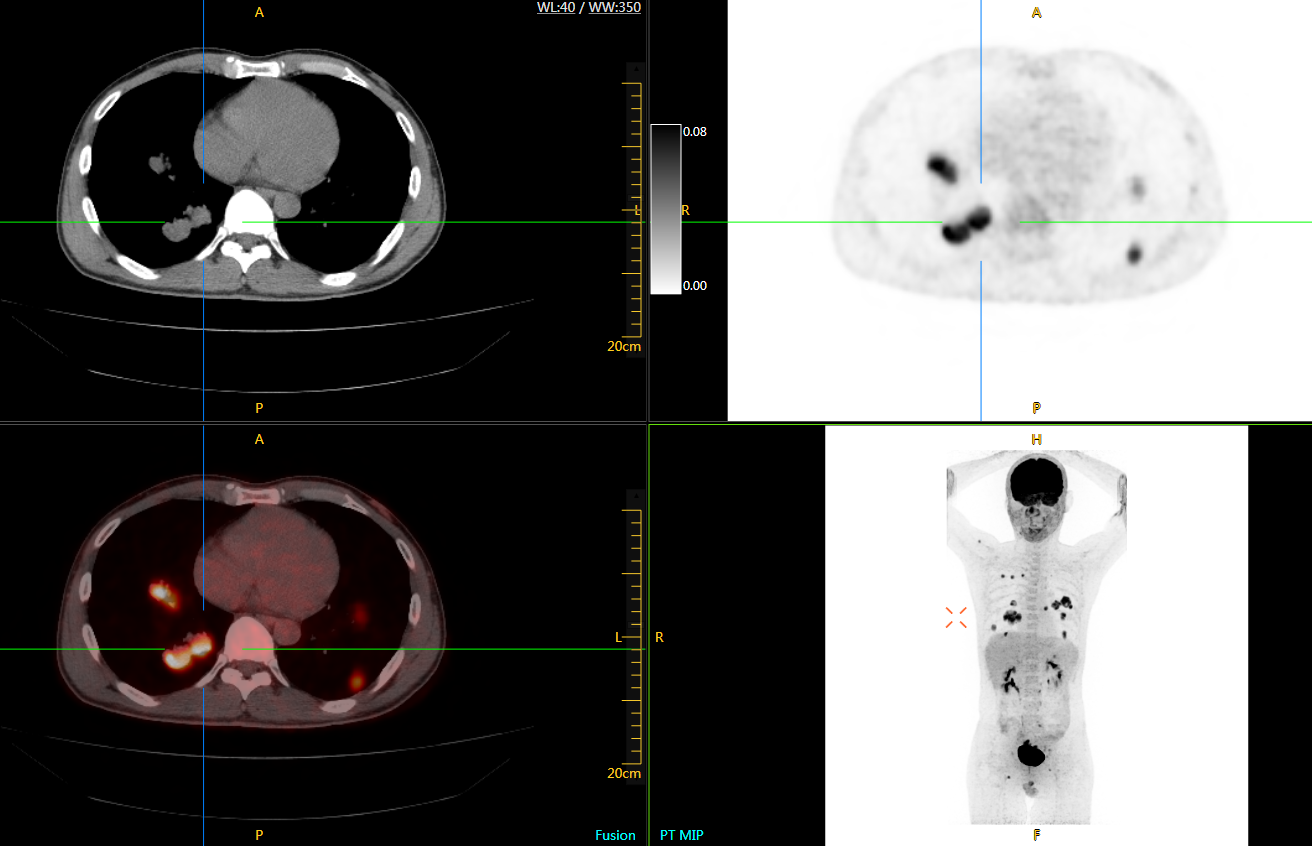

uExplorer探索者不再局限于傳統(tǒng)靜態(tài)代謝過程3D成像,而是在此基礎(chǔ)上新增一個維度——時間,從而實現(xiàn)4D全景成像。

注射總劑量為7.8mCi,14分鐘全身采集時間,在擁有超高靈敏度與超高分辨率的uEXPLORER上,即可得到展示顯示人體諸多精細(xì)結(jié)構(gòu)的高清三維圖像。

注射總劑量為7.8mCi,注射后1.6小時,基于uEXPLORER探索者掃描1分鐘的圖像